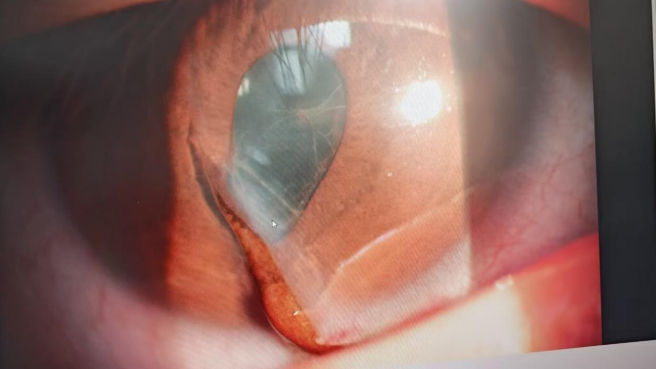

经眼科团队紧急检查,一个残酷的结论摆在了所有人面前:眼球破裂伤伴虹膜脱出。

这可是眼科三级手术范畴的急危重症!眼球破了,眼内的虹膜、

重要组织直接露在外面。如果不马上止住,感染一旦发生,孩子可能彻底失明,甚至面临摘除眼球的厄运。

清创、取出异物、精细还纳脱出的虹膜、缝合破裂的眼球壁……每一秒,都在和黑暗赛跑。